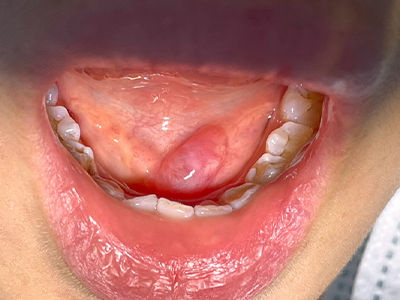

舌下腺囊肿下颌一侧长了大疙瘩图

舌下腺囊肿患者下颌区会出现一凸起的半球形肿物,外观形似大疙瘩,口底囊肿表现并不明显,触之柔软,与皮肤无粘连,可压缩,患者有明显的异物感。